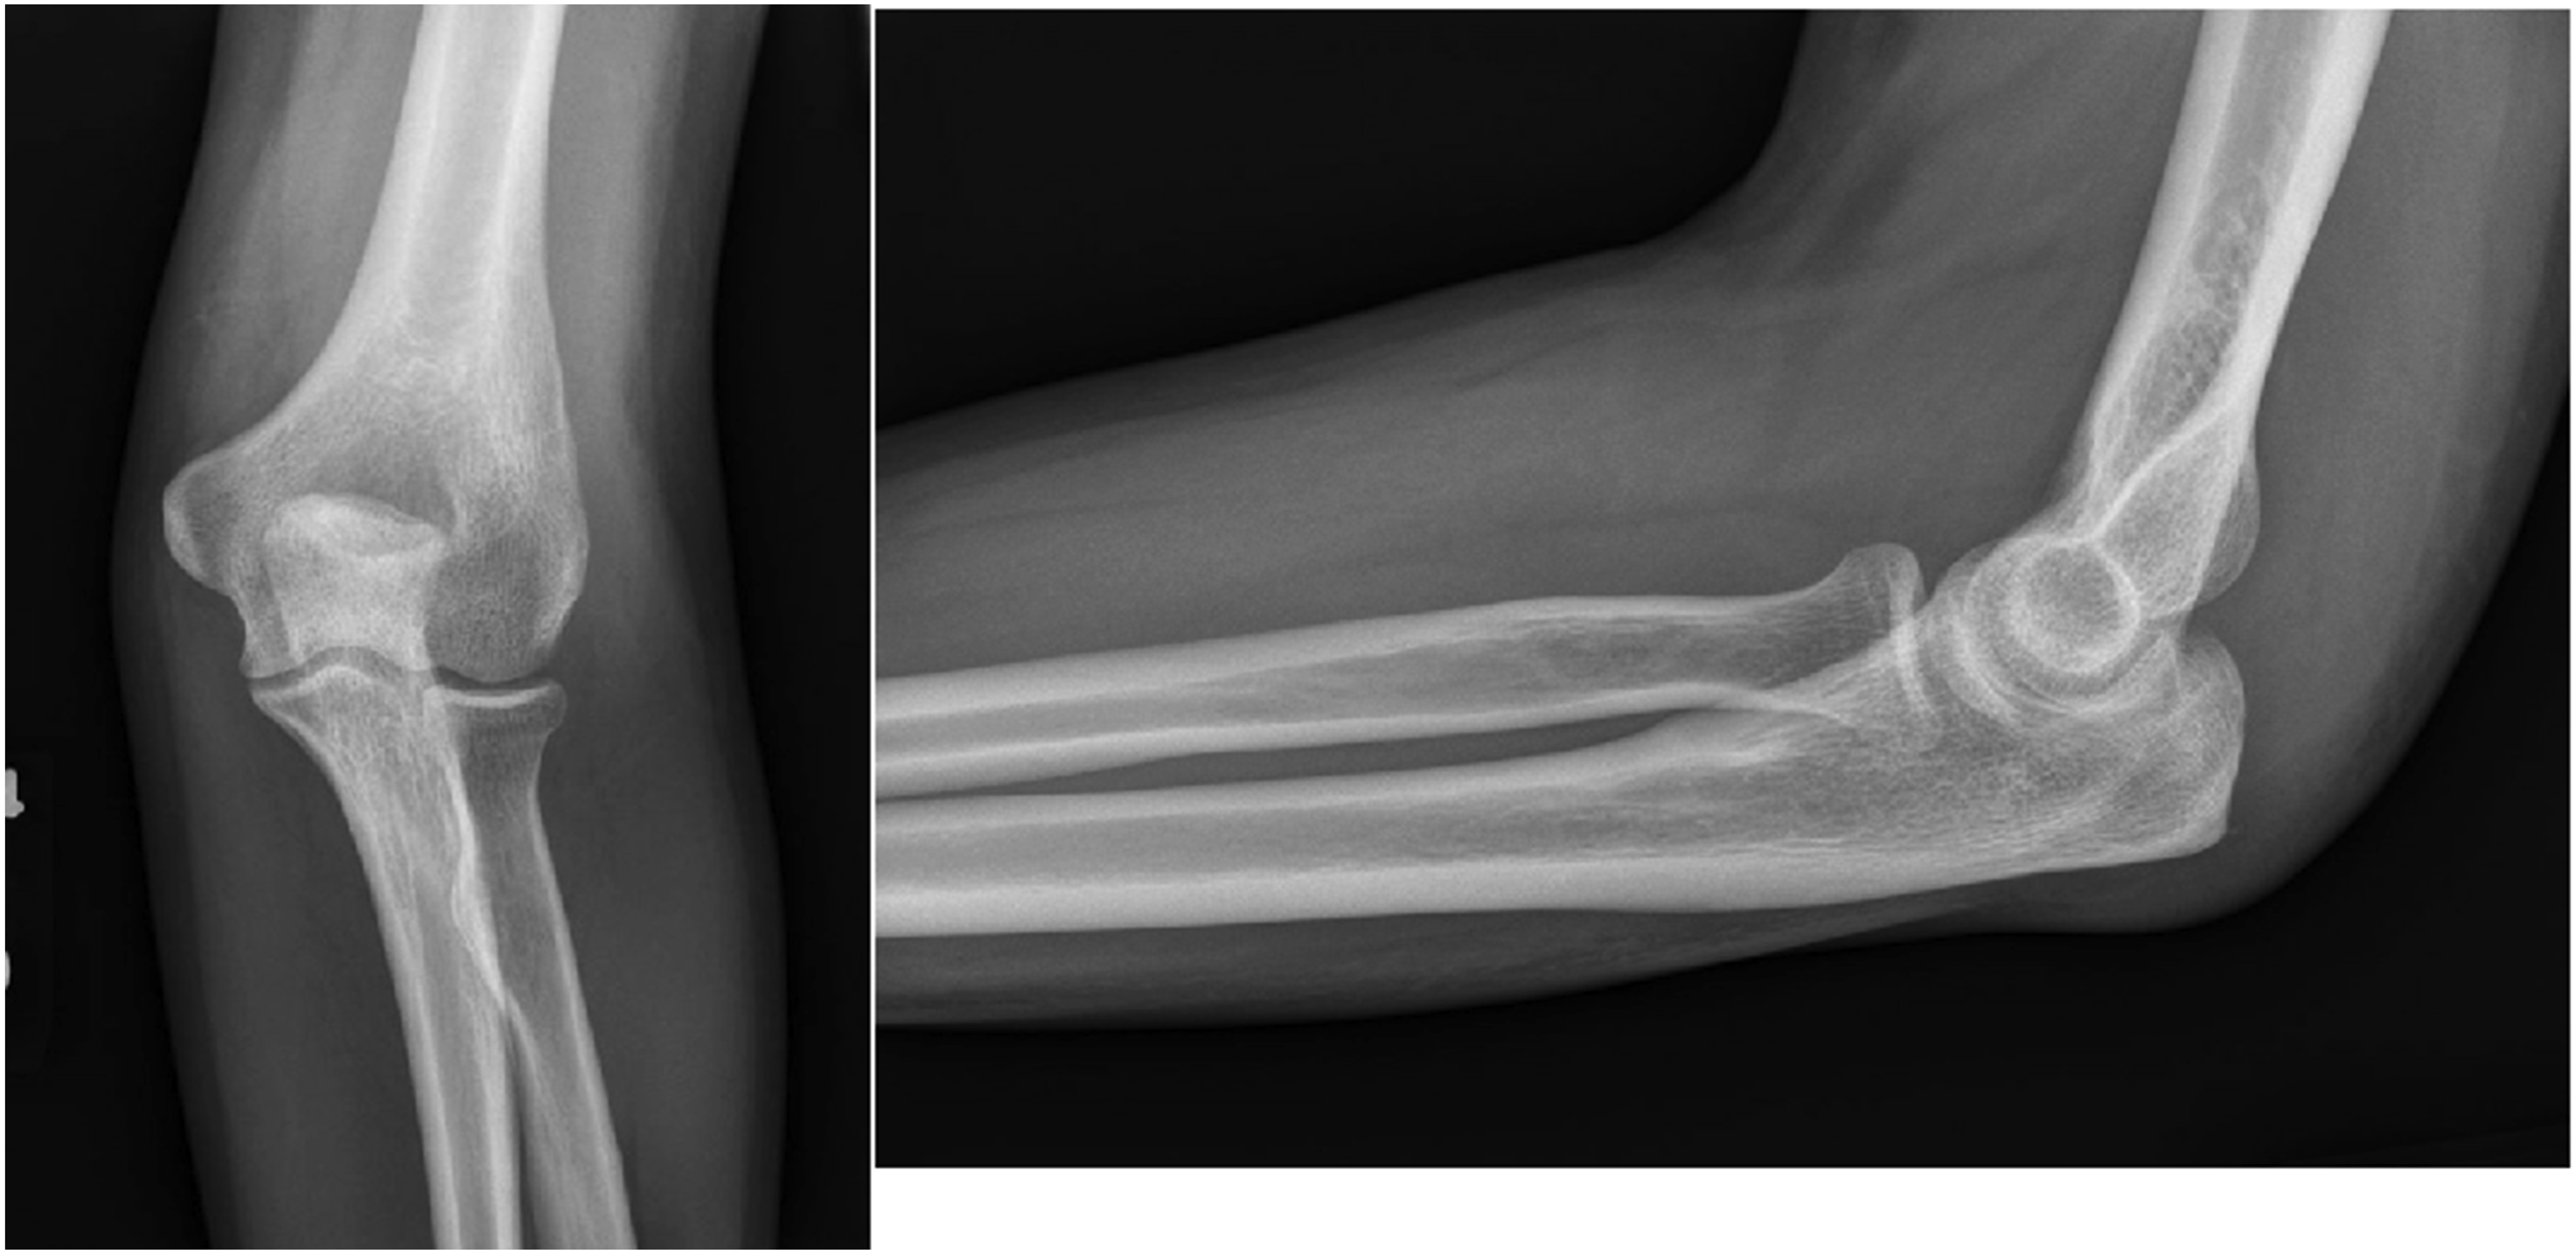

Two months later, he developed new-onset migratory polyarthritis involving the left elbow, bilateral ankles, knees, and small joints of both hands. At this time, the patient did not have any abdominal symptoms. Physical examination revealed joint swelling and tenderness. Radiographs of the right hand (Figure 1) and left elbow (Figure 2) obtained at this time demonstrated only soft tissue swelling, with no radiographic evidence of erosive or inflammatory arthritis, focal bone lesions, or bone infarction. MRI of the left elbow showed posterior subcutaneous and soft tissue edema with associated triceps muscle edema, a small joint effusion and mild bone marrow edema at the olecranon process (Figure 3). Synovial fluid aspirated from the left elbow showed mildly elevated white blood cell count (3000 cells/mm3), but Gram stain, culture, and crystal analysis were negative. Laboratory tests showed elevated ESR and CRP, normal serum uric acid, creatine kinase, and complement (C3 and C4) levels. Antinuclear antibody and rheumatoid factor were negative. Urine tests for Radiographs of the right hand demonstrating soft tissue swelling predominantly about the metacarpophalangeal joints. No osseous erosions, no focal lytic or sclerotic bone lesion. Radiographs of the left elbow demonstrating mild soft tissue swelling at the posterior elbow. No osseous abnormalities. Axial STIR MR images of the left elbow demonstrate subcutaneous edema, triceps muscle edema, small joint effusion and mild bone marrow edema at the olecranon process.